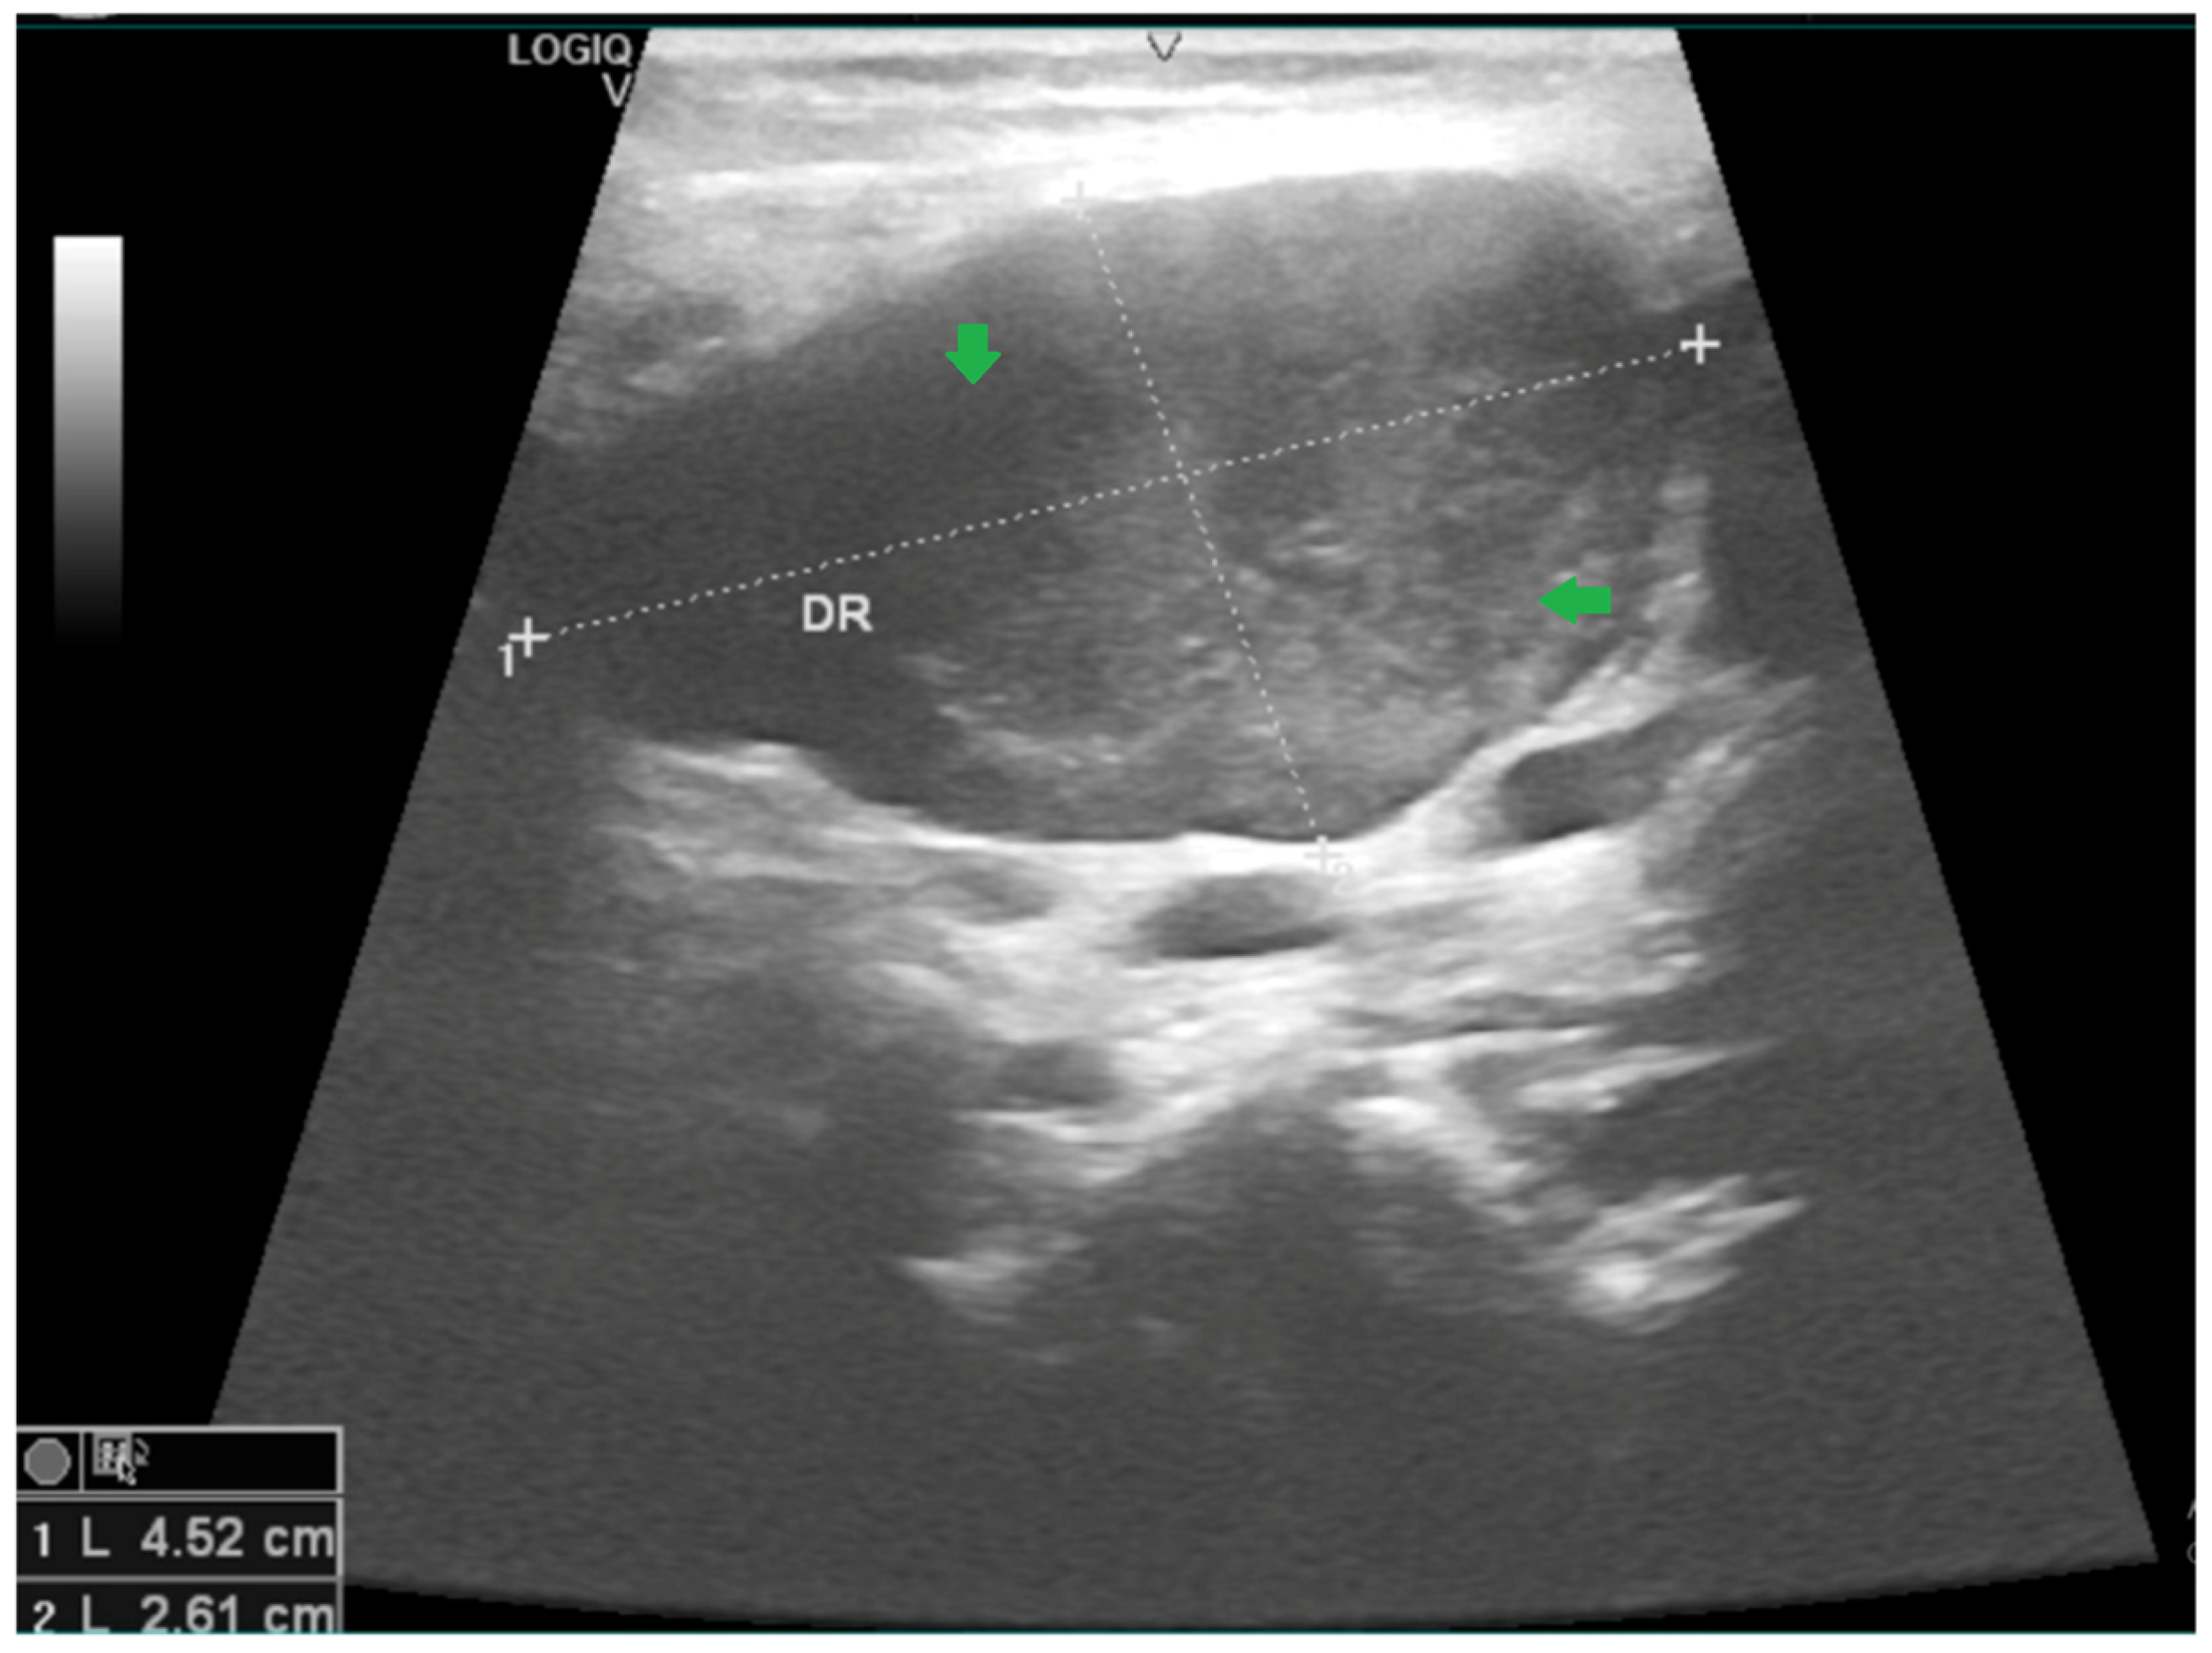

2.1. Case 1

2.2. Case 2